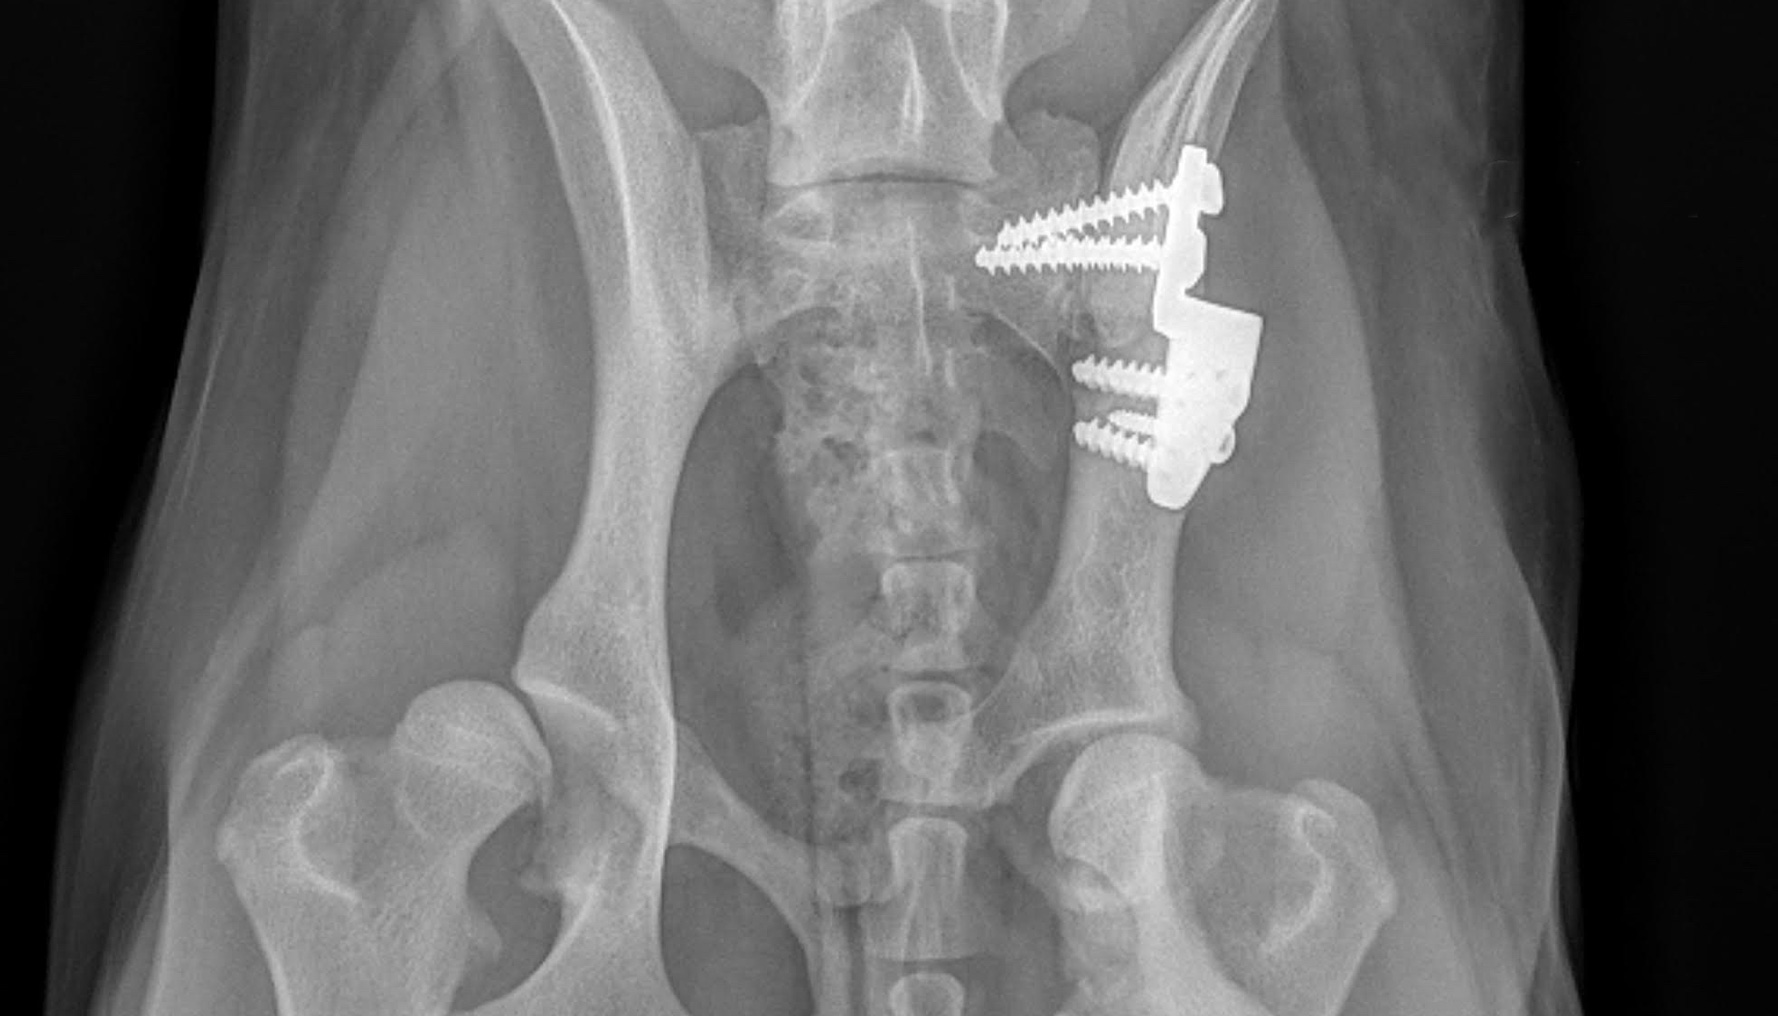

Orthopedic surgery

Orthopedic surgery is any surgery that involves your dog's skeletal system and the bones, joints, tendons, muscles, ligaments, and cartilage associated with it.